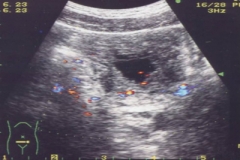

腺性膀胱炎的检查

随着生活质量不断提升,人们对于自身健康也越来越关注,定期体检也成了很多人的习惯,特别是对于一些危害性大的疾病,体检也成为及时阻止疾病恶化的关键。腺性膀胱炎是一种...